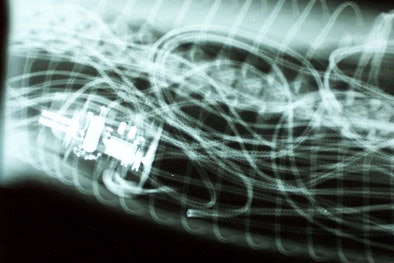

| Above and below: x-ray images show the tangle of the blanket's wiring extending through about 8 feet of a python's digestive tract. The surgery to remove it required an 18-inch incision. All images courtesy of St. Francis Pet Center. |